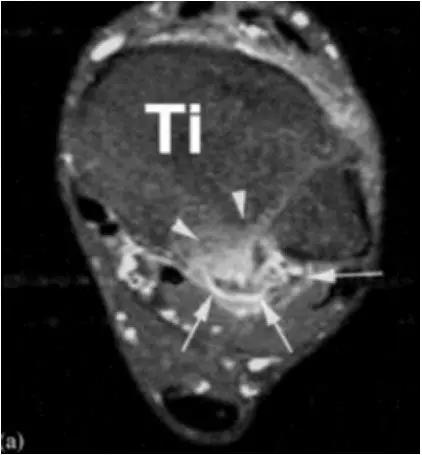

轴位示意图示后内侧撞击综合征:M:内踝;L:外踝;TP:胫后肌腱;FDL:趾长屈肌腱;Talus:距骨。短箭:距骨胫骨间肌腱深层纤维;箭头:距骨胫骨间肌腱后部纤维。

X线平片示胫骨后部骨赘形成,MR质子像黑箭示胫骨内后侧骨赘形成,白箭示内后侧软组织增厚, 白箭头:胫后肌腱;黑箭头:趾长屈肌腱